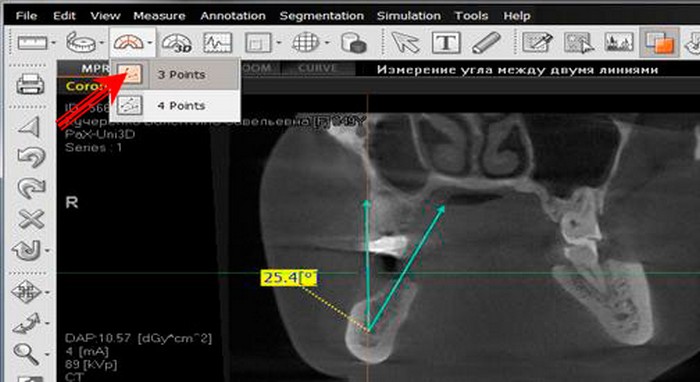

О самом кабинете рассказал его владелец, Александр Пономаренко:

- Мы арендуем это помещение и установили свое оборудование. Такого нет нигде в области из-за чего и была договоренность, чтобы поставить его в самой большой больнице. Привезли этот южнокорейских компьютерный томограф, который как для детей безвредный, так и для взрослых людей. Беременных снимаем, потому что у нас минимальная доза облучения. Работаем на таких же условиях как и все. Никто же велосипед не придумывал. Тем более, что мы и деньги пошли заплатили в банк и банковский чек им принесли.

- Мы очень часто посылаем людей сделать снимок именно там. Имея 3D-изображение мы можем на компьютере со всех сторон посмотреть зуб, корень, понять строение кости, заглянуть туда, куда обычным рентген аппаратом мы в принципе не сможем посмотреть. Если сравнивать его с обычным рентгеном, то обычный нам дает где-то 10% необходимой информации, в то время как 3D-изображение сделанное этим аппаратом — 100%.